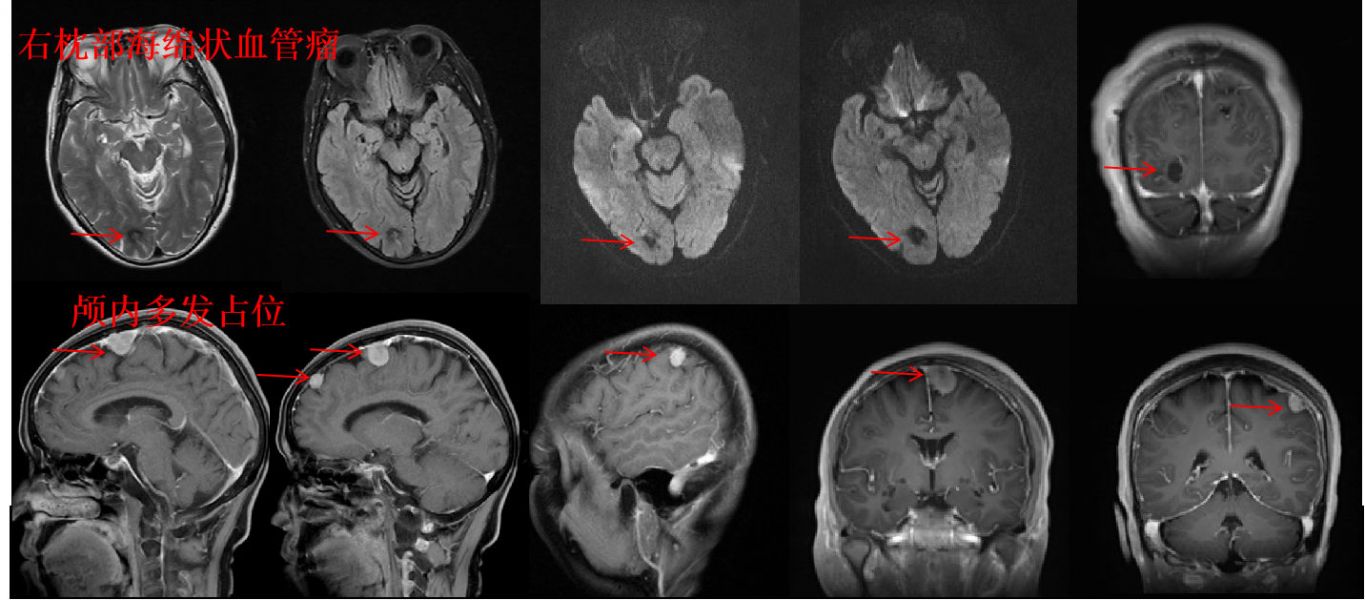

患者向某某,65岁,半年来反复头痛头晕并伴有视力下降,在当地医院以颈椎病诊治,效果不佳。近日,他慕名来到州人民医院就诊,神经外科二病区副主任田志接诊了该患者。通过颅脑磁共振平扫+增强检查,发现该患者是一例罕见的颅内海绵状血管瘤出血合并多发占位的病例。神经外科二病区主任朱英杰立即组织阅片讨论,认为患者主诉有视力下降改变,磁共振提示右侧枕叶呈典型“爆米花”样影像学表现,符合海绵状血管瘤反复出血的征象。另外,患者左侧大脑半球存在三处占位性病灶,增强提示考虑为脑膜瘤可能性大。

颅内海绵状血管瘤合并占位的,全球统计人年发病率不足0.01%,发病率极低。在黄纯海副院长的带领下,神经外科二病区高度关注该病例,通过认真分析病情,认为患者海绵状血管瘤已反复出血,且造成了神经功能受损,仍有再次出血可能,病情势必会进一步加重,手术治疗才是唯一的治疗手段。另外,患者颅内还有三处占位性病灶,均位于重要功能区,黄纯海认为,虽然该患者的病情复杂,但仍可以通过精确的定位实现手术切除达到治疗效果。

神经外科二病区利用最新的三维成像技术,结合术前的混合现实技术,为患者进行精确的病灶定位,并依此个性化设计手术方案,在麻醉科的协助下,朱英杰主任对患者进行了海绵状血管瘤显微切除合并占位显微切除手术。因术前定位准确,手术创伤小,大大降低了病灶再出血的风险,术后通过医护人员的精心治疗和护理,现患者恢复良好,视力明显好转,没有出现任何并发症。